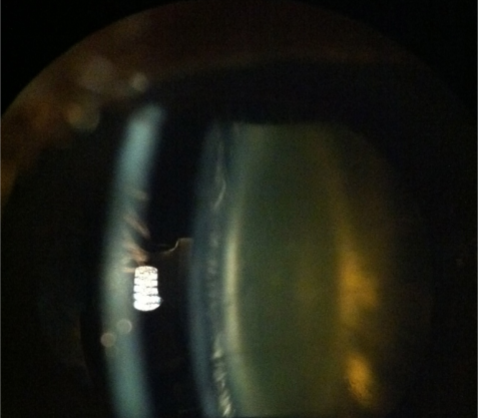

cortical (cuneiform) cataract

wedge-shaped opacities in anterior & posterior cortex

slowly progressive

begins inferior-nasal quadrant

signs/sx:

increased glare

decreased contrast sensitivity

variable VA reduction (depends on if spokes go through visual axis)

lenticular, lamellar clefts-spoke opacities

sheet-like zones of peripheral opacification

cortical cataract

NS & cortical cataract